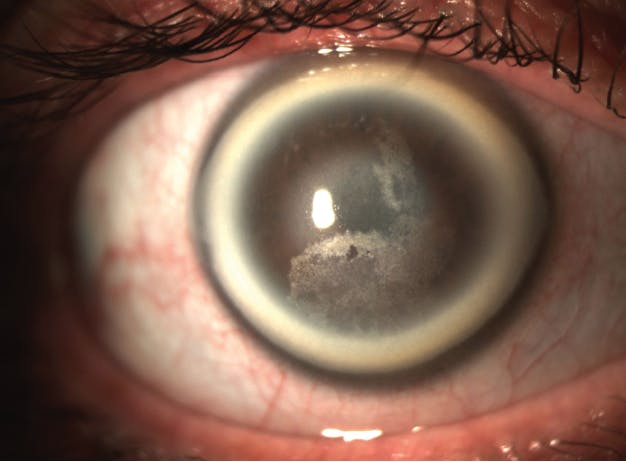

Schnyder corneal dystrophy (SCD) is a rare, progressive corneal disorder caused by abnormal accumulations of lipid and cholesterol. The condition results in corneal opacification and premature or early arcus. Patients with SCD may also have subepithelial crystal deposition (Figure 2). Familial hypercholesterolemia is the most common lipoprotein abnormality in patients with SCD, with some reports suggesting that up to two-thirds of SCD patients have the disorder.8 The causative gene for SCD is UBIAD.8,9